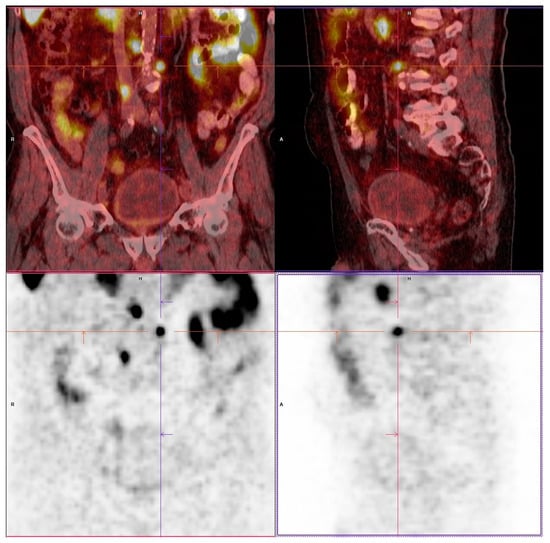

2. Materials and Methods

3. Results